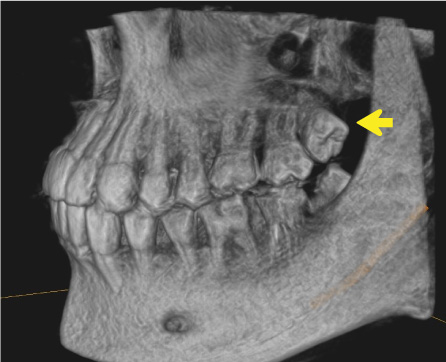

一般歯科診療では敬遠されがちな、重要神経管(下歯槽神経管:下顎の神経と動脈・静脈が入っている管)に接する親知らず

抜く方向や角度を十分にシミュレーションして安全抜歯を心がけている。

上の親知らずには、歯並びと逸脱した方向に生えてしまうものが多くあります。

これらは、咬み合わせに悪影響を及ぼすだけでなく、周囲の歯の虫歯や歯周病の原因となってしまうことがあります。

これらを安全に抜歯することも口腔外科の仕事です。